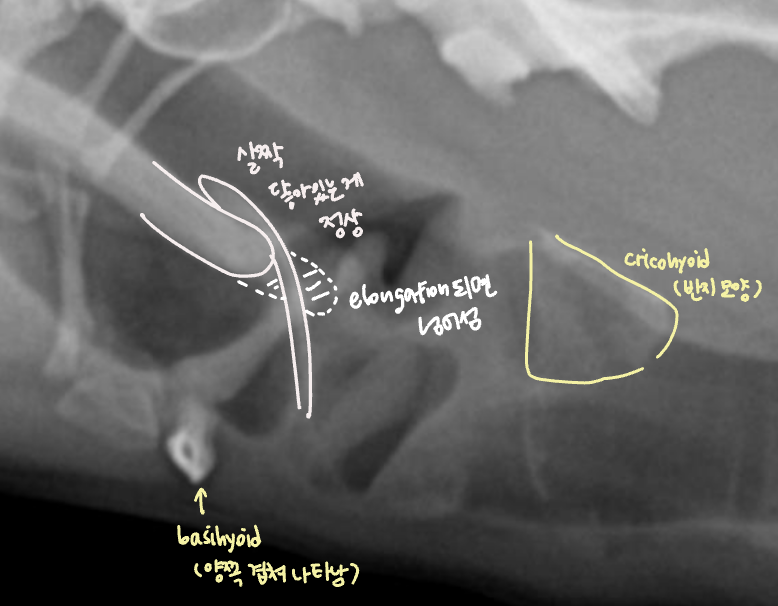

- soft palate edema & elongation (연구개노장)

- laryngeal edema, saccules, collapase, paralysis

- (dynamic) pharyngeal collapse